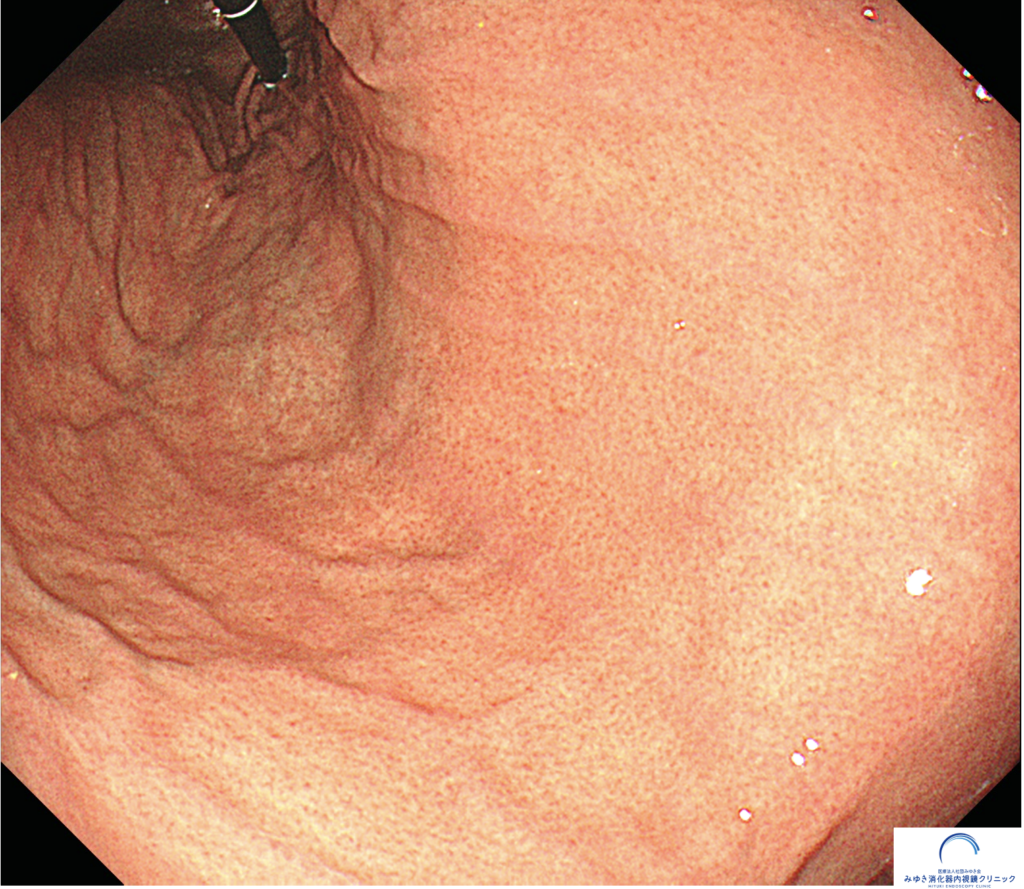

当院で行った胃カメラ検査では、正常な胃粘膜は全体的にきれいで、正常な胃粘膜と考えられる所見でした。胃体部にはRAC(ラック)が明瞭に確認でき、ピロリ菌感染を疑う所見は認められませんでした。

① つやつやした粘膜

胃カメラで見える正常な胃の粘膜は、光沢があり、ツヤがあります。また胃のひだも細く真っ直ぐに伸びています。